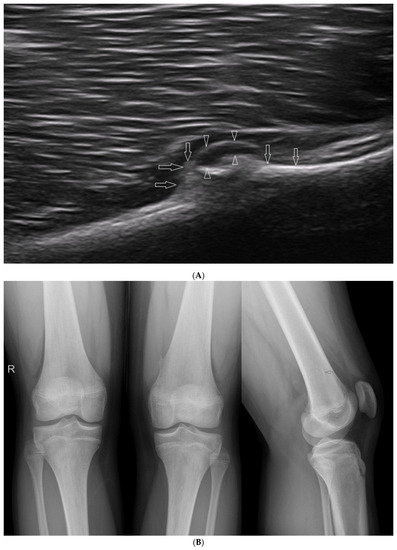

3.2.6. Exudates and Inflammations Affecting Joints

3.2.5. Osteochondroma